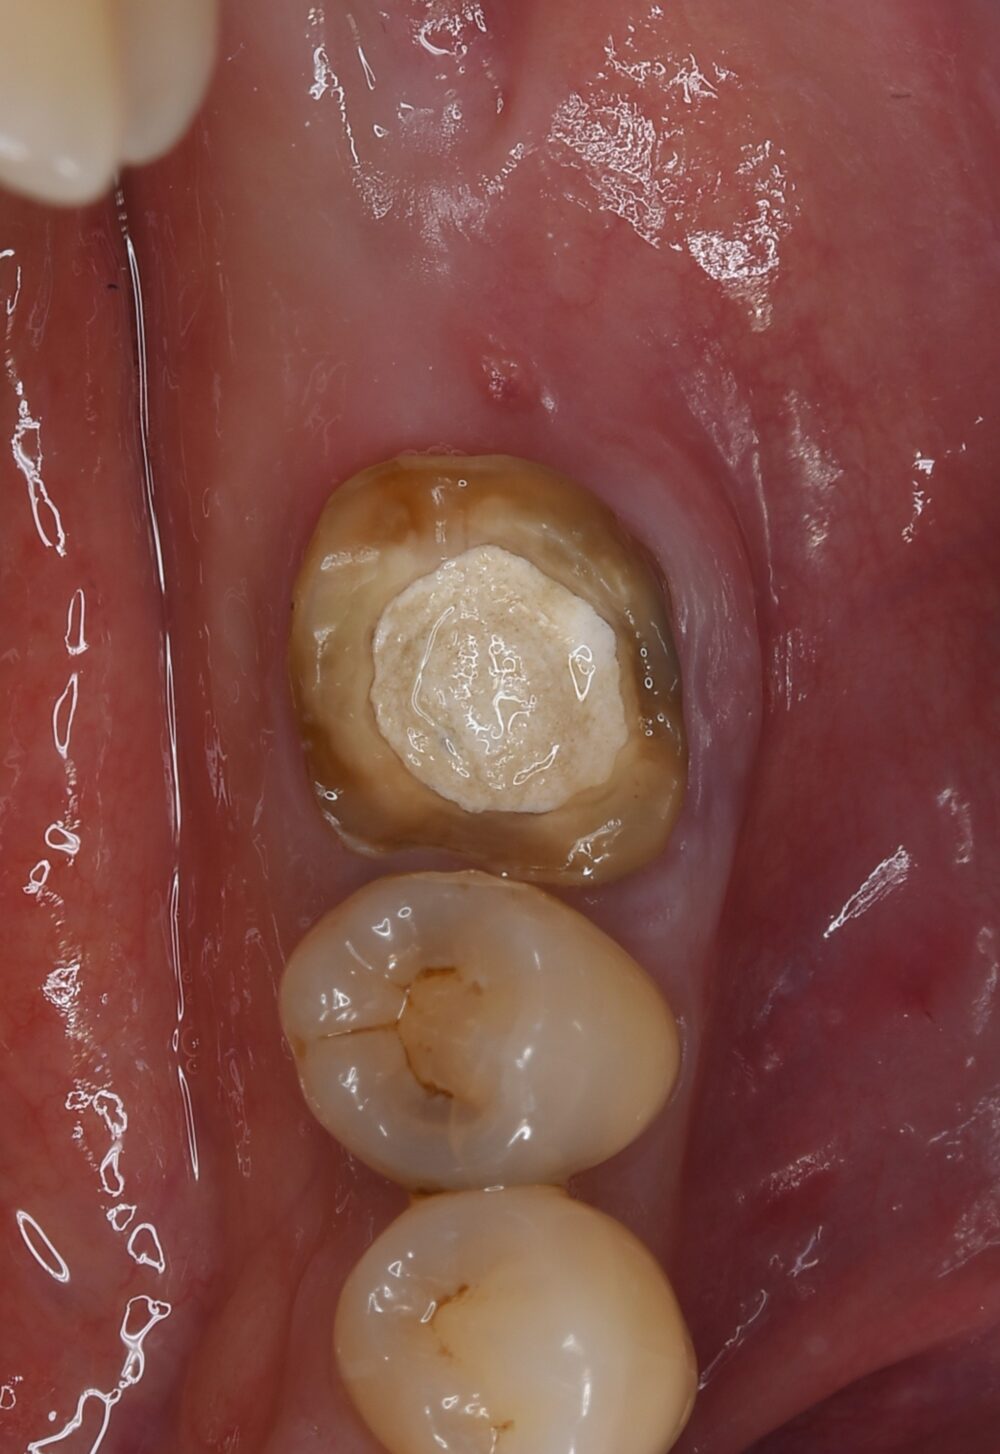

症例4

右下親知らずを右下第二大臼歯へ移植

| 患者様データ | 20代 女性 |

| 来院時の主訴 | 「右下奥歯で噛むと痛い。」 |

| 医院の診断 | 歯根破折 |

| 治療費 | 総額:255,000円(税抜) 【内訳】 歯牙移植150,000円、ファイバーポストコア20,000円、セラミック治療85,000円 |

| リスクと副作用 | ①根管治療歯は長期的には破折するリスク ②長期的なメインテナンスが必要 ③歯根の外部吸収 |

抜歯が必要になった際に余っている親知らずがあれば移植歯として利用することができます。 術前に撮影したCT画像から3Dプリンターを用いて親知らずのレプリカを作製することで、親知らずが乾燥することを防ぎ、成功率が上がるよう努力しています。 |